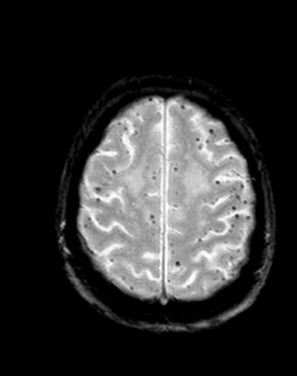

White matter lesions, old hemorrhages (hemosiderin) can only be depicted with MRI.

At many times the collecting term, angioma is used for these lesions: capillary teleangiectasias, cavernosus angiomas, arteriovenosus malformations.

Vascular anomalies can be depicted reliably with MRI, even without the use of contrast medium.